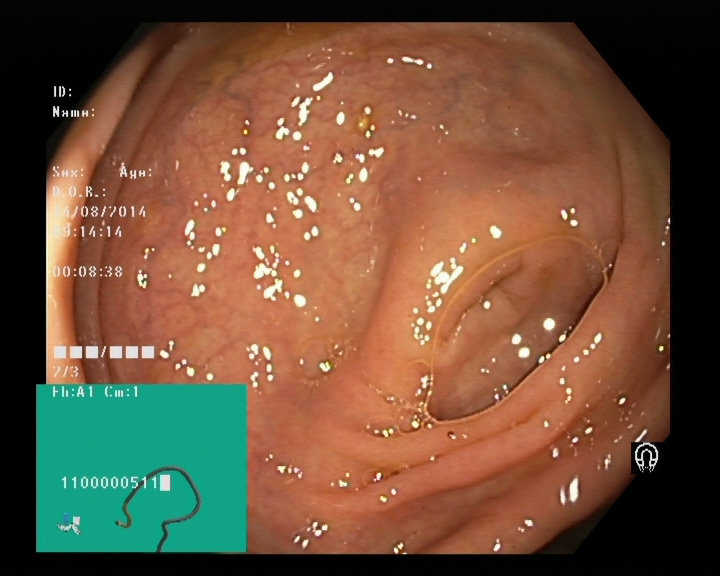

The Nerthus Dataset

BBPS 3

BBPS 2

BBPS 1

BBPS 0